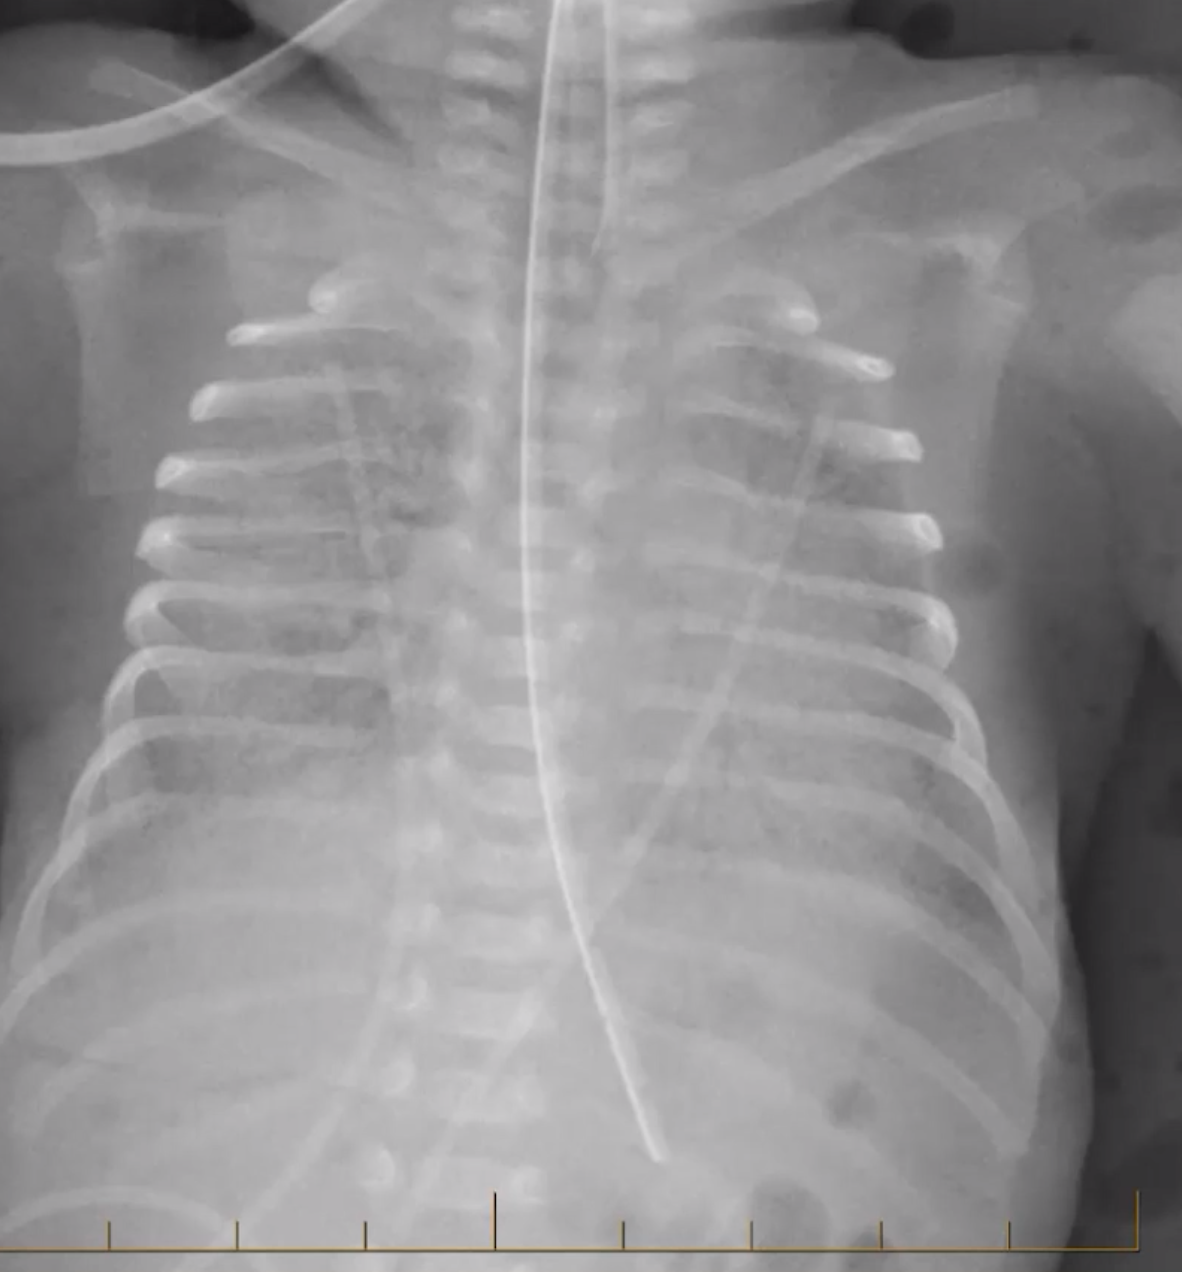

Pulmonary Interstitial Emphysema

• Ventilation in patients with surfactant deficiency causes alveoli to pop and air to escape

• Bubbly or linear lucencies

• Imaging findings seen at first week of life

• <4 weeks old (note BPD >4 weeks old)